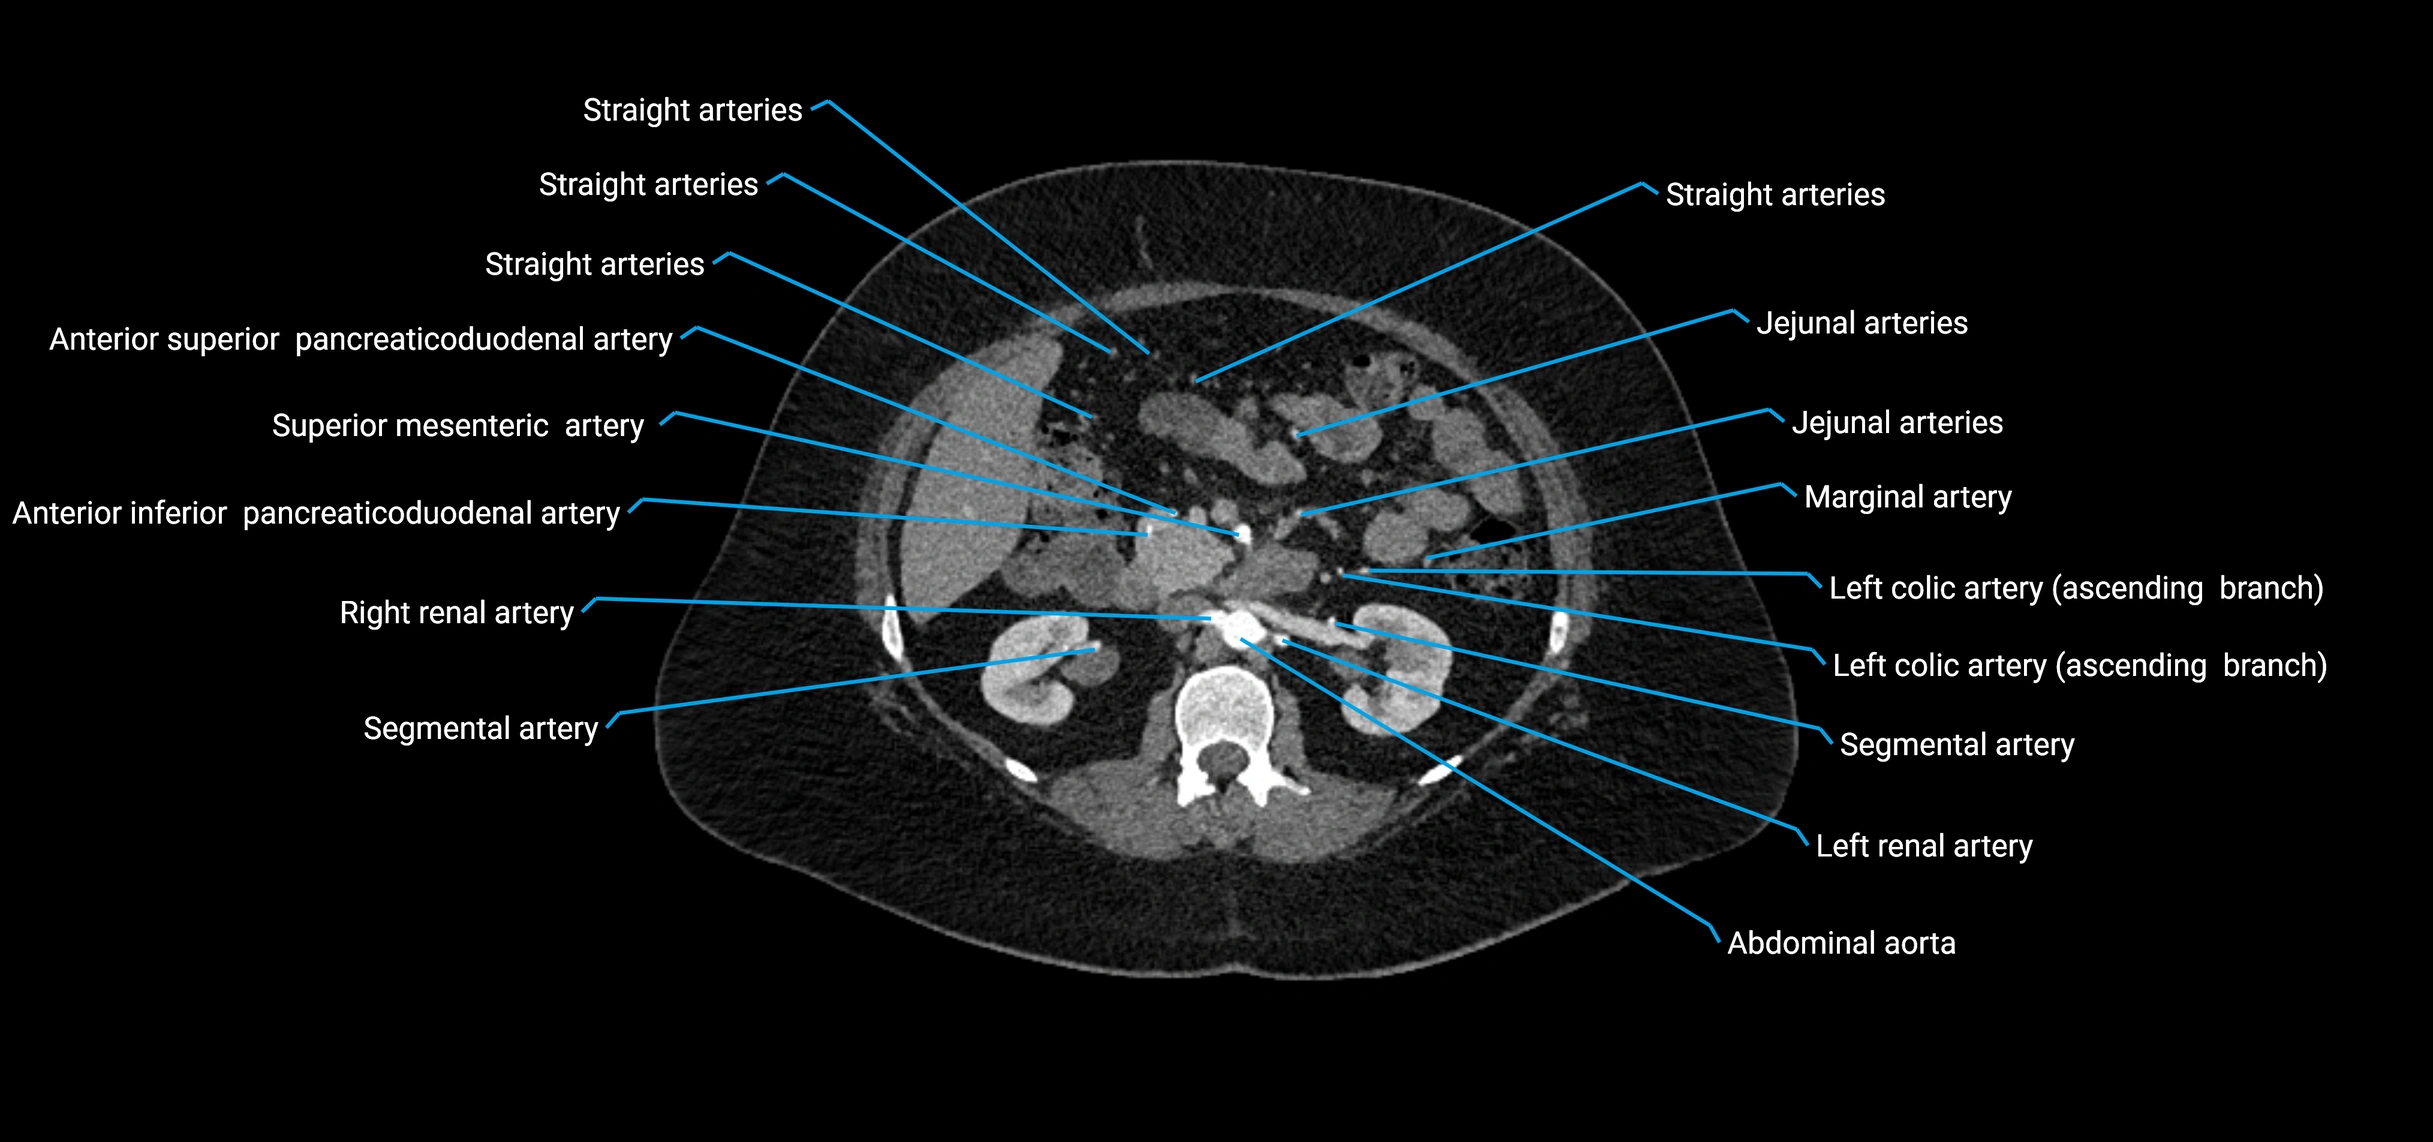

Contrast-enhanced CT (CTA):

• Gold standard for abdominal aortic imaging

• Provides excellent detail of lumen, wall, aneurysm, thrombus, and branch vessels

• Multiplanar and 3D reconstructions help in aneurysm measurement, stent graft planning, and dissection evaluation

• Detects acute rupture, traumatic injury, or occlusion with high sensitivity